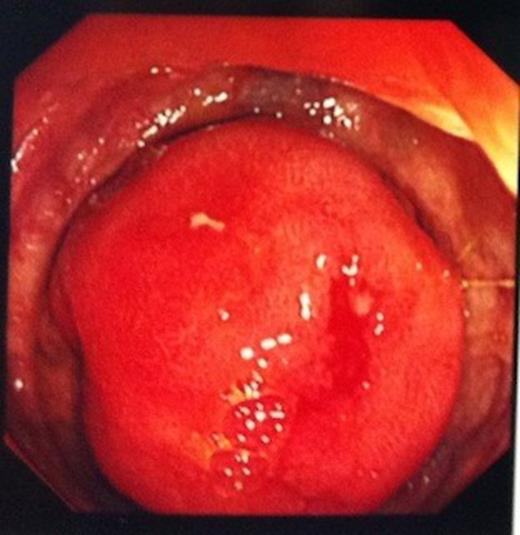

A 74 year old man was referred to our endoscopy unit after a positive faecal occult blood test. He had no preceeding symptoms or history that would place him at increased risk of colorectal cancer. At colonoscopy, excellent views were obtained to the ileocaecal valve (ICV) and appendix orifice, confirming identification of the caecum. With no colonic pathology seen, the endoscopist proceeded to intubate the ICV, as part of his routine practice. A 3cm ileal polyp was identified 5cm proximal to the valve (Figure 1) and biopsies were taken.

Histology demonstrated features of a classical neuroendocrine carcinoid tumour infiltrating the muscularis mucosa.